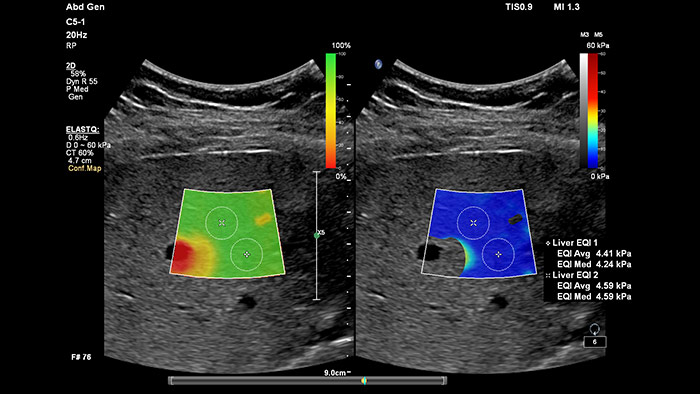

Elastografía por onda transversal de imágenes con ElastQ

La elastografía por ultrasonidos de onda transversal ofrece un método no invasivo, reproducible y fácil de poner en práctica para evaluar la rigidez tisular. Los estudios realizados apuntan a que, en lugar de un costoso y doloroso procedimiento de biopsia, una sencilla exploración por ultrasonidos con elastografía de onda transversal podría convertirse en el procedimiento habitual para evaluar el estado de las enfermedades hepáticas. La elastografía por onda transversal de alto rendimiento de las imágenes con ElastQ incluye la evaluación cuantitativa de la rigidez tisular, codificada con colores, en extensas regiones de interés (ROI) en tiempo real. Las imágenes con ElastQ también ofrecen la posibilidad de efectuar mediciones retrospectivas en imágenes almacenadas; además, una exclusiva pantalla con un mapa de confianza emplea el análisis inteligente para ofrecer la garantía adicional de que las mediciones del usuario se han obtenido en zonas tisulares con una propagación adecuada de ondas transversales.

Evaluación hepática no invasiva simplificada

La medición de la rigidez hepática se obtiene en cuestión de segundos por medio de una sencilla exploración no invasiva.